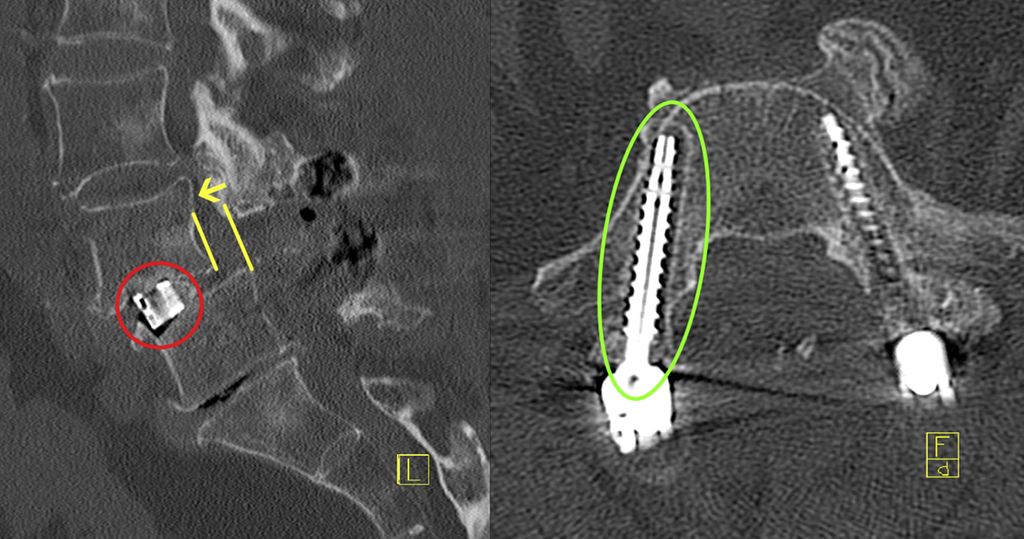

Lässt sich ein Assessment präoperativ zeit- oder strukturbedingt nicht durchführen, können jedoch bereits vorliegende bildgebende Befunde als Informationsquelle genutzt werden. Ein Beispiel ist der MRT-basierte Vertebral Bone Quality Score (VBQ), der im Jahr 2021 von Ehresman et al. beschrieben wurde.9 Die Ermittlung des Wertes wird in Abb. 1 erläutert. Ein anderes Beispiel stellt die Bestimmung der Hounsfield Units (CT-HU) aus einem CT-Scan dar. Ein eindeutiger Cut-off-Wert für den VBQ-Score liegt noch nicht vor, rezente Daten legen jedoch eine Grenze bei ca. 2,4 nahe.10Grundsätzlich besteht eine gute Inter-Rater-Variabilität und die Korrelation mit DEXA-Werten ist gegeben, jedoch kann der VBQ-Score keine DEXA-Messung ersetzen.11 Im Alltag stellt er allerdings eine einfache Möglichkeit dar, Informationen zur Knochendichte zu erlangen, wenn keine rezente DEXA-Messung vorliegt.

Abb. 1: Ermittlung des MRT-basierten Vertebral Bone Quality Score (VBQ) nach Ehresman J et al.9